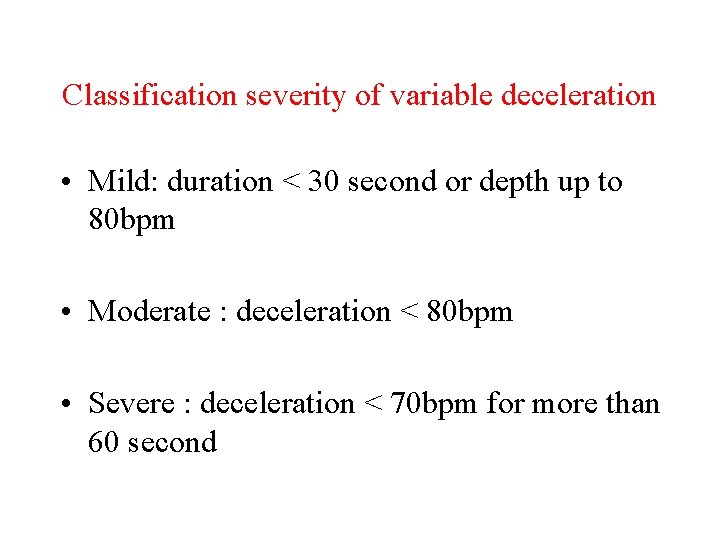

Classification severity of variable deceleration • Mild: duration < 30 second or depth up to 80 bpm • Moderate : deceleration < 80 bpm • Severe : deceleration < 70 bpm for more than 60 second